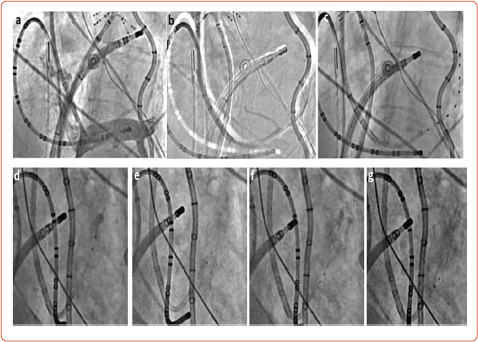

在这篇综述中,作者描述了不断发展的房颤管理替代策略,重点是非侵入性和经皮自主调节。这种调节可以通过耳屏刺激、肾去神经支配、心脏传入去神经支配、马歇尔静脉酒精注射、压力感受器激活疗法和心内膜神经节丛消融术等方法来实现。虽然这些疗法很有前景,但目前仍在研究中,但在不久的将来,它们可能在联合传统肺静脉隔离治疗房颤中发挥作用。

In this review, the authors describe evolving alternative strategies for the management of AF, focusing on non-invasive and percutaneous autonomic modulation. This modulation can be achieved - among other approaches - via tragus stimulation, renal denervation, cardiac afferent denervation, alcohol injection in the vein of Marshall, baroreceptor activation therapy and endocardial ganglionated plexi ablation. Although promising, these therapies are currently under investigation but could play a role in the treatment of AF in combination with conventional pulmonary vein isolation in the near future.